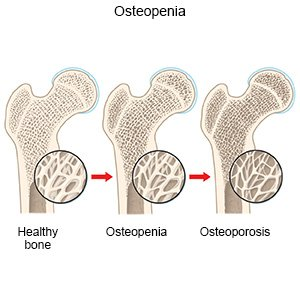

What is Osteoporosis? Osteoporosis is a condition that weakens bones. As a result, bones become thin and fragile. This means they can break easily, even

Bone health is crucial for strong and supportive bodies. It’s about ensuring our bones don’t become brittle and weak. But what about things like bone